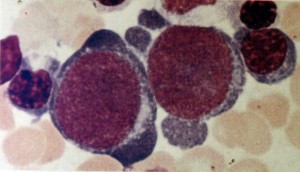

Pronormoblasto (proeritroblasto). É o mais imaturo, no entanto, é a maior célula da eritropoiese. Seu núcleo é esférico, de coloração violeta-amarronado, que tem uma estrutura de cromatina altamente empacotada com núcleos azulados difíceis de serem distinguidos. Citoplasma é palidamente azulado com manchas ou áreas brilhantes em forma de foice aguda (hialoplasma), dependendo da localização da zona do Complexo de Golghi e das mitocôndrias. A tendência a dando mecânico produz extrusão plasmática. Na mitose, o avivamento da cor é causado pela distribuição difusa das mitocôndrias por todo citoplasma.

Macroblasto (macropronormoblasto): formas celulares resultantes da chamada divisão hemi-heteroplástica do pronormoblasto, ao qual assemelha-se morfologicamente, sendo distinguida apenas pelo diâmetro menor da célula. A composição do núcleo pode ter densidade variada, assim como certas transições para os tipos celulares formados nas etapas seguintes da eritropoiese.